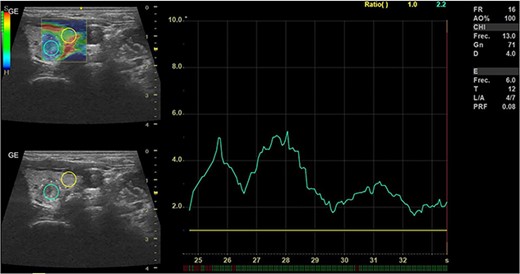

In May 2022, a thyroid ultrasound revealed a solid isoechoic left lobe TN measuring 12 × 11 × 13 mm, characterized by microcalcifications and irregular borders (Fig. 1). The color-flow Doppler ultrasound indicated increased perfusion, leading to its classification as a TI-RADS 5 nodule (Fig. 2). Elastography yielded a value of 2.2 (Fig. 3). Fine-needle aspiration confirmed Bethesda VI, consistent with thyroid papillary carcinoma.

Doppler thyroid ultrasound: transversal view, left lobe nodule doppler. Pre-RFA procedure.